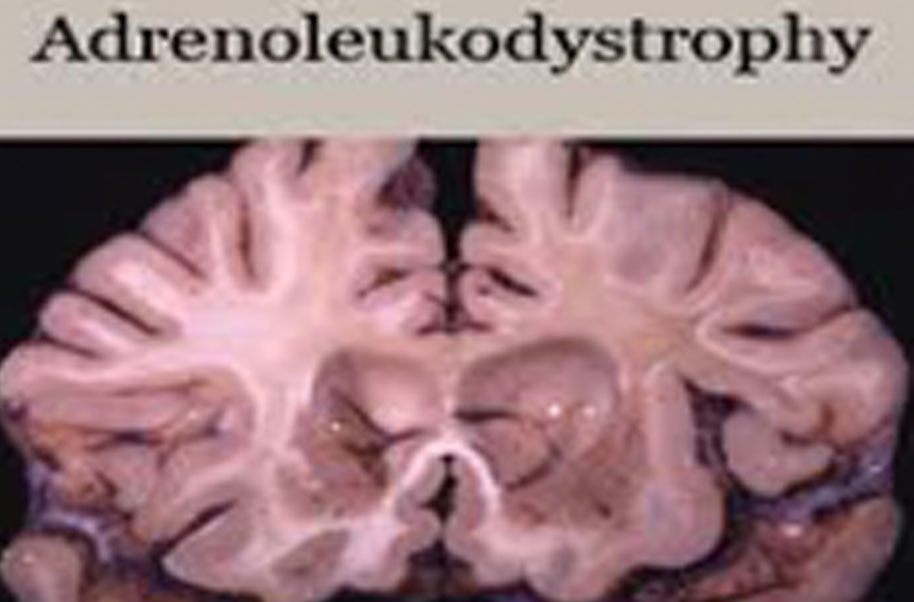

Ald is one of a group of genetic disorders called the leukodystrophies that cause damage to the myelin sheath of the nerve fibers in the brain. The myelin sheath is a fatty covering which acts as an electrical insulator and there are three types of ald.